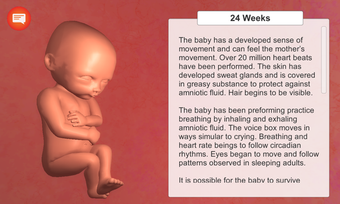

Esta aplicación está diseñada para ayudar a las madres y padres a entender los cambios que están ocurriendo en su cuerpo durante el embarazo. También está diseñada para ayudarles a hacer un seguimiento del desarrollo de su bebé en el útero. Es muy fácil de usar y la interfaz es muy simple e intuitiva. Muestra las etapas clave del embarazo desde la concepción hasta el nacimiento.

La aplicación está dividida en varias secciones, y cada sección contiene una descripción detallada y varios modelos 3D de alta calidad de las etapas clave del desarrollo del embarazo. Es muy fácil navegar por las secciones, y se puede cambiar entre ellas para ver diferentes etapas.